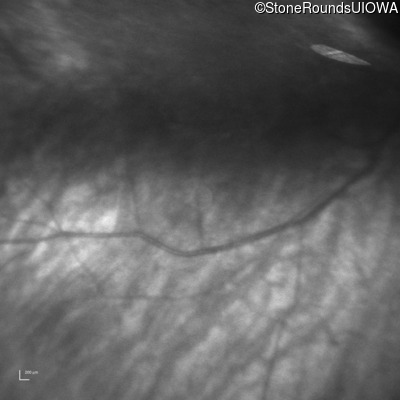

Infrared Fundus Photograph - Left -

Light Perception

Exemplar